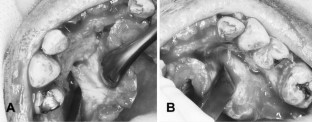

Fig. 3